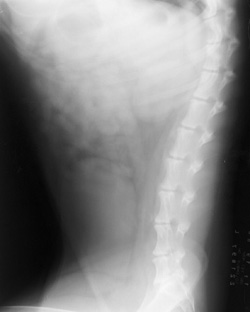

Motion

Patient motion resulting in a blurred image.